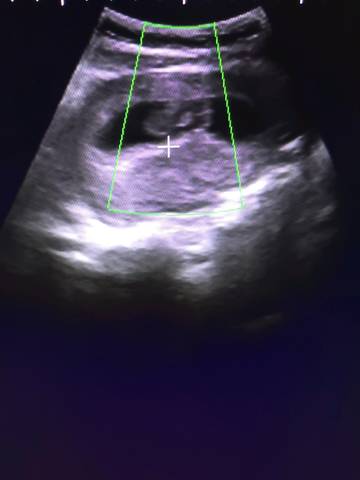

孕晚期做胎心监护要注意些什么?

答:胎心监护是对胎宝宝的心率变化进行检测,以便医生可以正确评估胎宝宝的安危状况。要想顺利、准确地做...